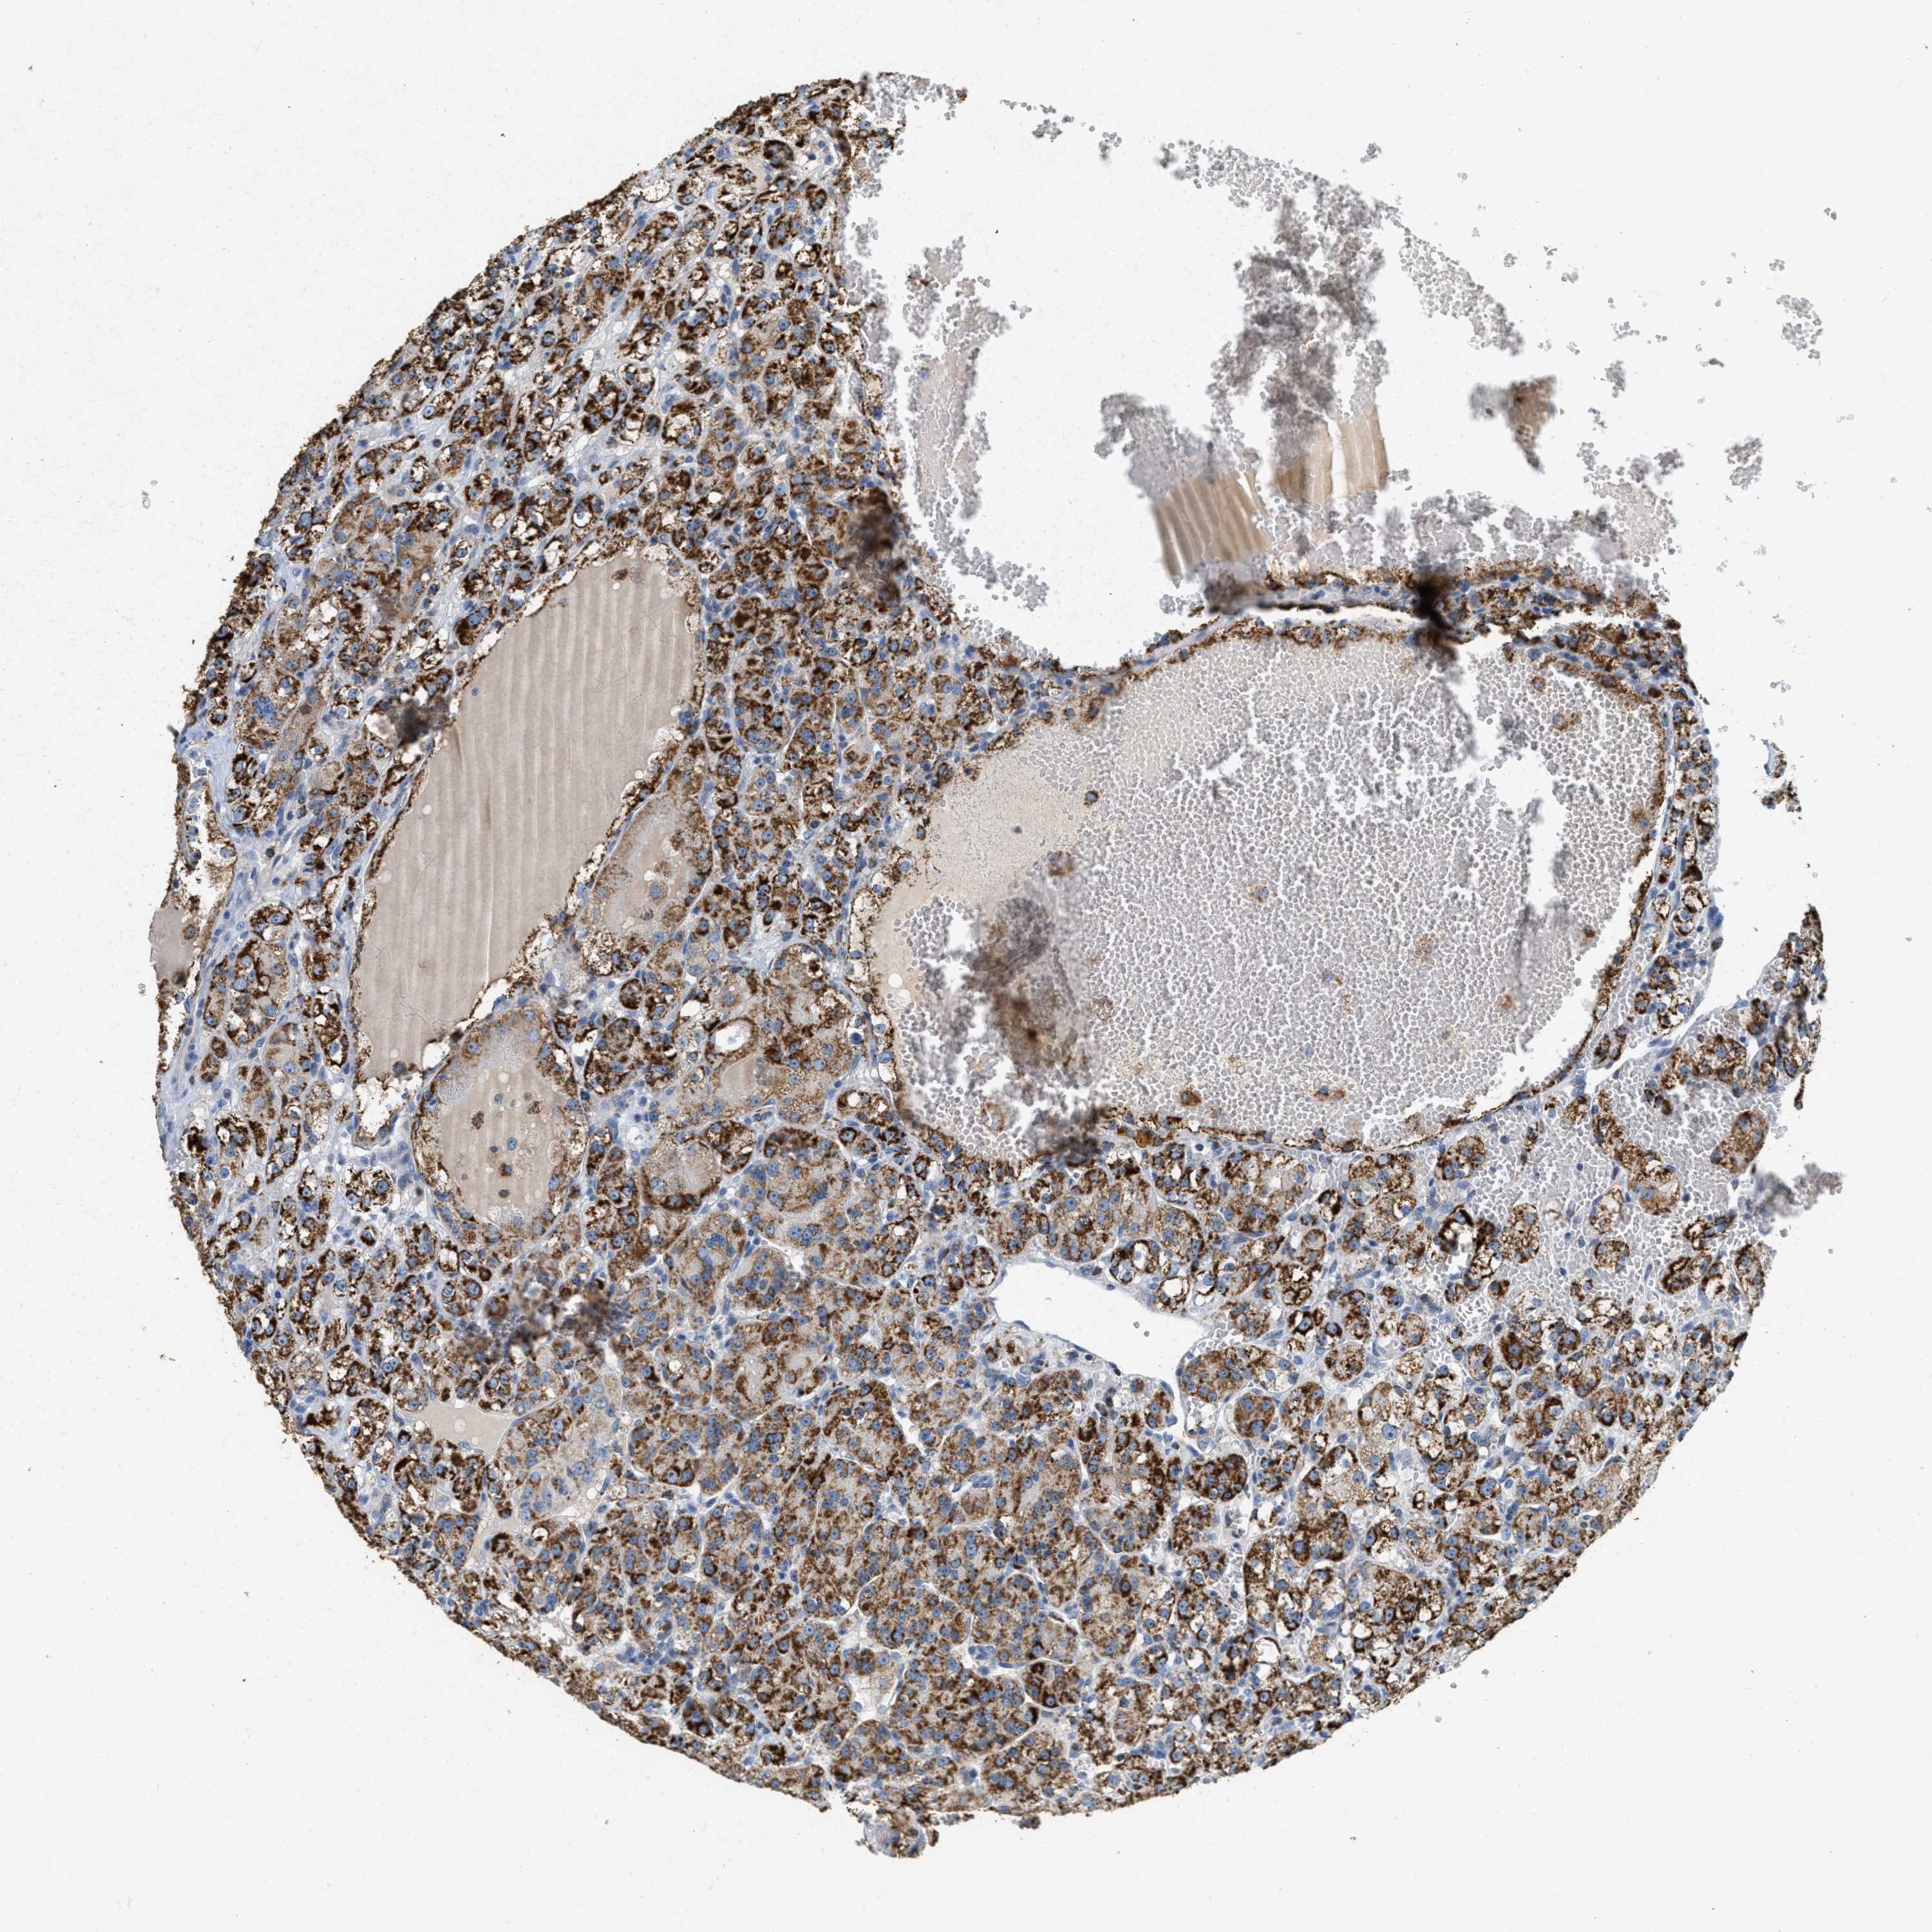

CANCER RENAL CANCER Show tissue menu

KICH TCGA KIRC TCGA KIRC VALIDATION KIRP TCGA PROTEIN RCC CPTAC PROTEIN EXPRESSION

KIDNEY CHROMOPHOBE (TCGA) - Interactive survival scatter ploti

The Survival Scatter plot shows the clinical status (i.e. dead or alive) for all individuals in the patient cohort, based on the same data that underlies the corresponding Kaplan-Meier plots. Patients that are alive at last time for follow-up are shown in blue and patients who have died during the study are shown in red.

The x-axis shows the expression levels (FPKM) of the investigated gene in the tumor tissue at the time of diagnosis. The y-axis shows the follow-up time after diagnosis (years). Both axes are complimented with kernel density curves demonstrating the data density over the axes. The top density plot shows the expression levels (FPKM) distribution among dead (red) and alive patients (blue). The right density plot shows the data density of the survived years of dead patients with high and low expression levels respectively, stratified using the cutoff indicated by the vertical dashed line through the Survival Scatter plot. This cutoff is automatically defined based on the FPKM cutoff that minimizes the p-score. The cutoff can be changed by dragging the vertical line or by entering a cutoff value in the square labeled "Current cut-off".

Under the Survival Scatter plot the p-score landscape (black curve; left axis) is shown together with dead median separation (red curve; right axis). Dead median separation is the difference in median mRNA expression between patients who have died with high and low expression, respectively. It is calculated as follows: median FPKM expression of dead patients with high expression - median FPKM expression of dead patients with low expression. This is intended to aid the user in visually exploring custom cutoffs and the associated p-scores and dead median separation.

Individual patient data is displayed and can be filtered by clicking on one or more of the category buttons on the top of the page. Categories describing expression level and patient information include: high, low, alive, dead, female, male and tumor stages. The scale of the x-axis can be toggled between linear and log-scale by clicking on the "x log" button. Mouse-over function shows TCGA ID, patient information and mRNA expression (FPKM) for each patient.

& Survival analysisi

Kaplan-Meier plots summarize results from analysis of correlation between mRNA expression level and patient survival. Patients were divided based on level of expression into one of the two groups "low" (under cut off) or "high" (over cut off). X-axis shows time for survival (years) and y-axis shows the probability of survival, where 1.0 corresponds to 100 percent.

HLCS is not prognostic in Kidney Chromophobe (TCGA)